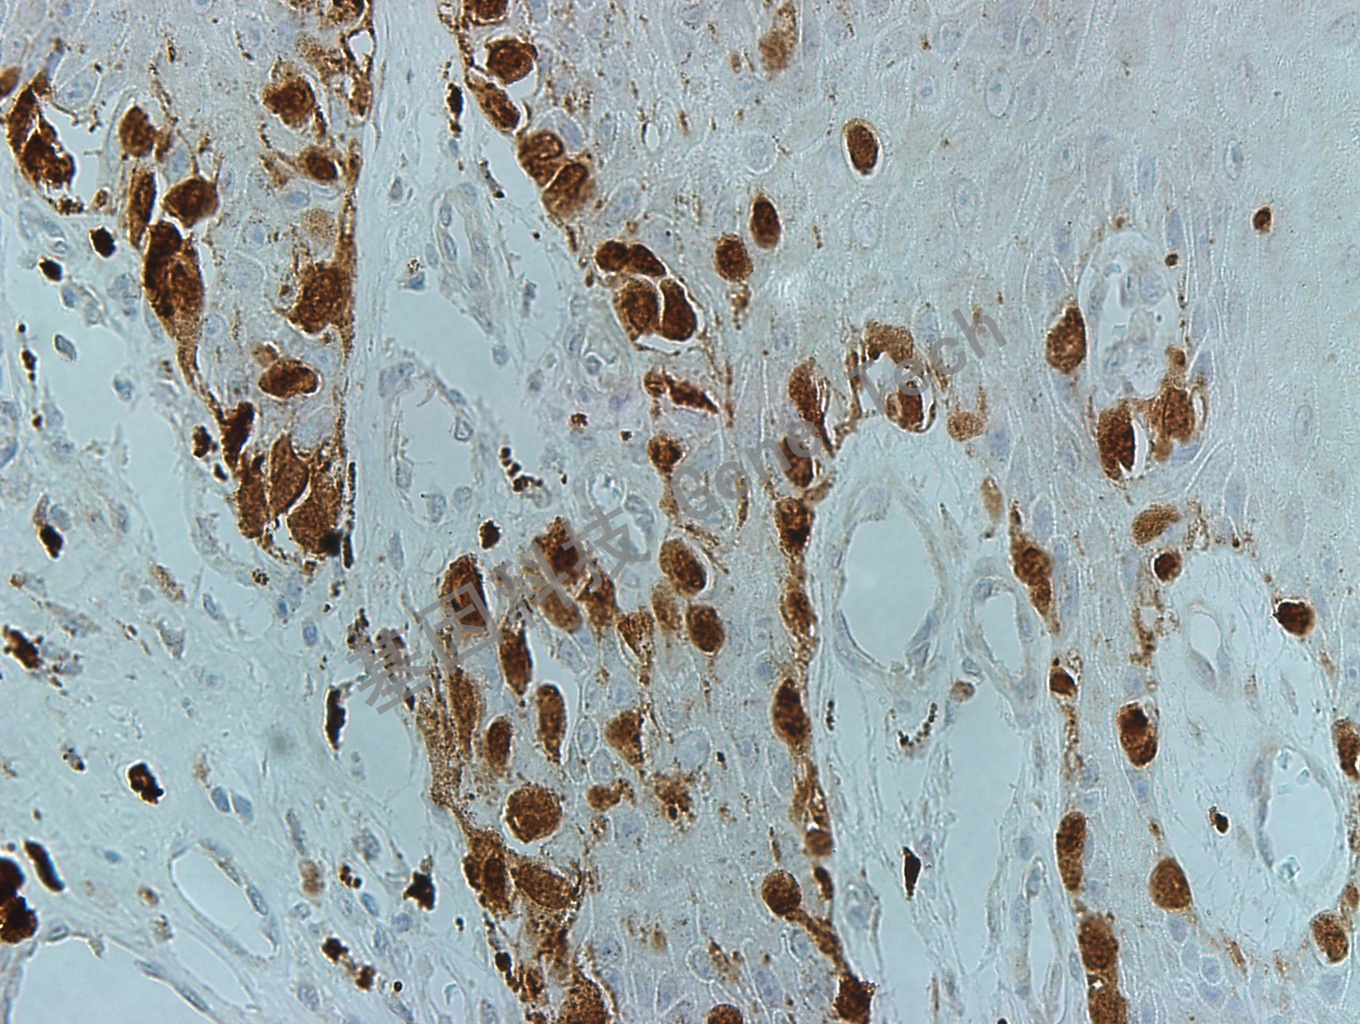

| 黑色素瘤石蠟切片,用 MiTF(GT2263)染色,細(xì)胞核陽(yáng)性,DAB 顯色。 | ||

| 預(yù)處理:高pH熱修復(fù) | 陽(yáng)性部位:細(xì)胞核 | 陽(yáng)性對(duì)照:黑色素瘤 |

| 簡(jiǎn)介:MiTF(Microphthalmia-associated transcription factor, 小眼畸形相關(guān)轉(zhuǎn)錄因子)是重要的轉(zhuǎn)錄因子。MiTF在色素細(xì)胞的發(fā)育、分化和功能調(diào)節(jié)中發(fā)揮關(guān)鍵性作用,不僅是黑色素細(xì)胞生長(zhǎng)、分化及色素生成的主要調(diào)節(jié)蛋白,對(duì)黑色素細(xì)胞的惡性轉(zhuǎn)化以及黑素瘤的發(fā)生、發(fā)展及轉(zhuǎn)移亦發(fā)揮重要的作用。MiTF也與肥大細(xì)胞和骨骼發(fā)育密切相關(guān)。MiTF除表達(dá)于黑色素細(xì)胞及腫瘤,在巨噬細(xì)胞、破骨細(xì)胞和多種腫瘤也可能陽(yáng)性。主要用于惡性黑色素瘤的診斷。 | ||